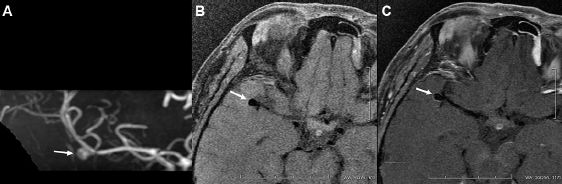

图1.右侧大脑中动脉分叉部的动脉瘤(A),增强前(B)后(C)相比,瘤壁无增强。

图2.右侧大脑中动脉分叉部的动脉瘤(A),与增强前(B)相比,增强后可见瘤壁完全增强(C)。